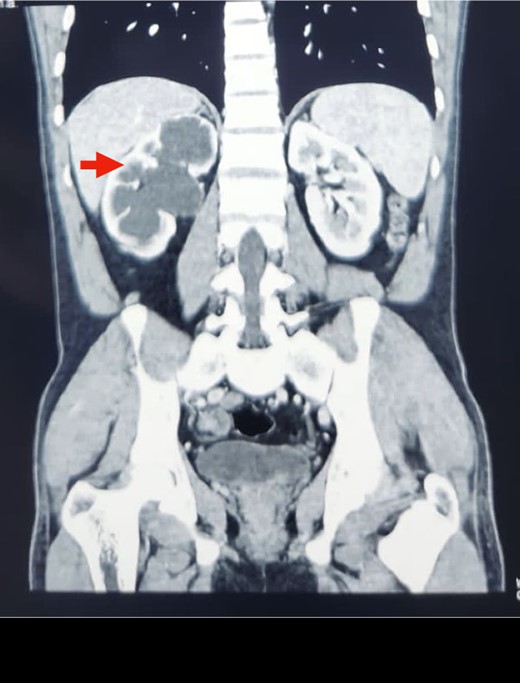

An abdominal ultrasound was done, which revealed moderate right-sided hydronephrosis and proximal dilated ureter. A routine X-ray kidney–ureter–bladder (KUB) showed no obvious radio opaque shadow in the renal pelvis. A contrast-enhanced computed tomography (CECT) KUB was done, which showed moderate right Hydroureteronephrosis (Fig. 1) extending to the proximal ureter with papillary necrosis, consistent with retrocaval ureter (Fig. 2).

Reconstruction image of CECT KUB showing retrocaval ureter (arrow) and hydronephrosis of right kidney with dilated proximal ureter.